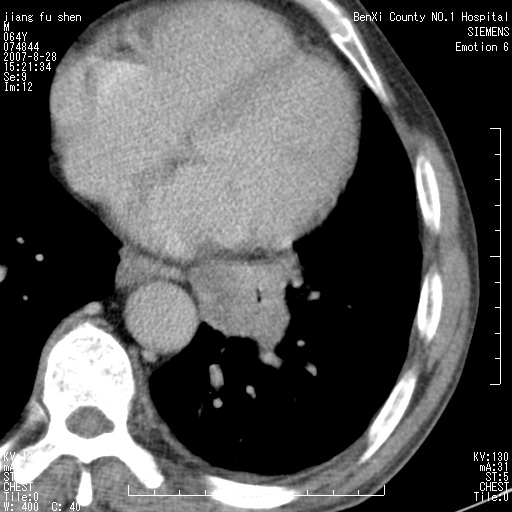

男、64、咳嗽、发烧一周、左肺呼吸音稍弱。既往肺结核,右手结核。

本次扫描患者未带原片,左肺下叶发现病灶。左肺上叶空洞,5组淋巴结肿大,1cm左右。

平扫20-33hu

增强31-33hu

1分半44-52

2分55-67

左肺下叶前内基底段支气管明显偏心性狭窄,周围分叶状肿块,伴有阻塞性肺炎,支持肺癌可能性大。